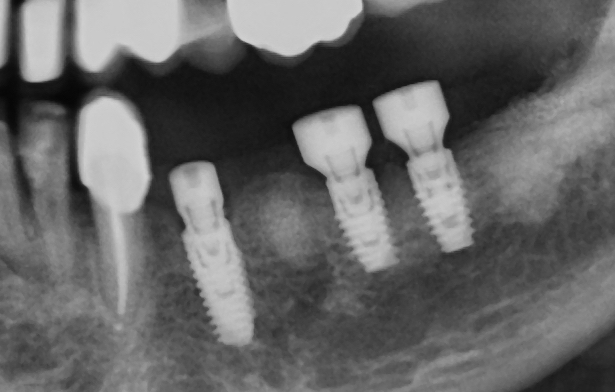

Το εμφύτευμα τοποθετείται μέσα στο οστό της γνάθου.

Για τους επόμενους 3–4 μήνες παραμένει καλυμμένο από τα ούλα, ώστε να ολοκληρωθεί η οστεοενσωμάτωση.